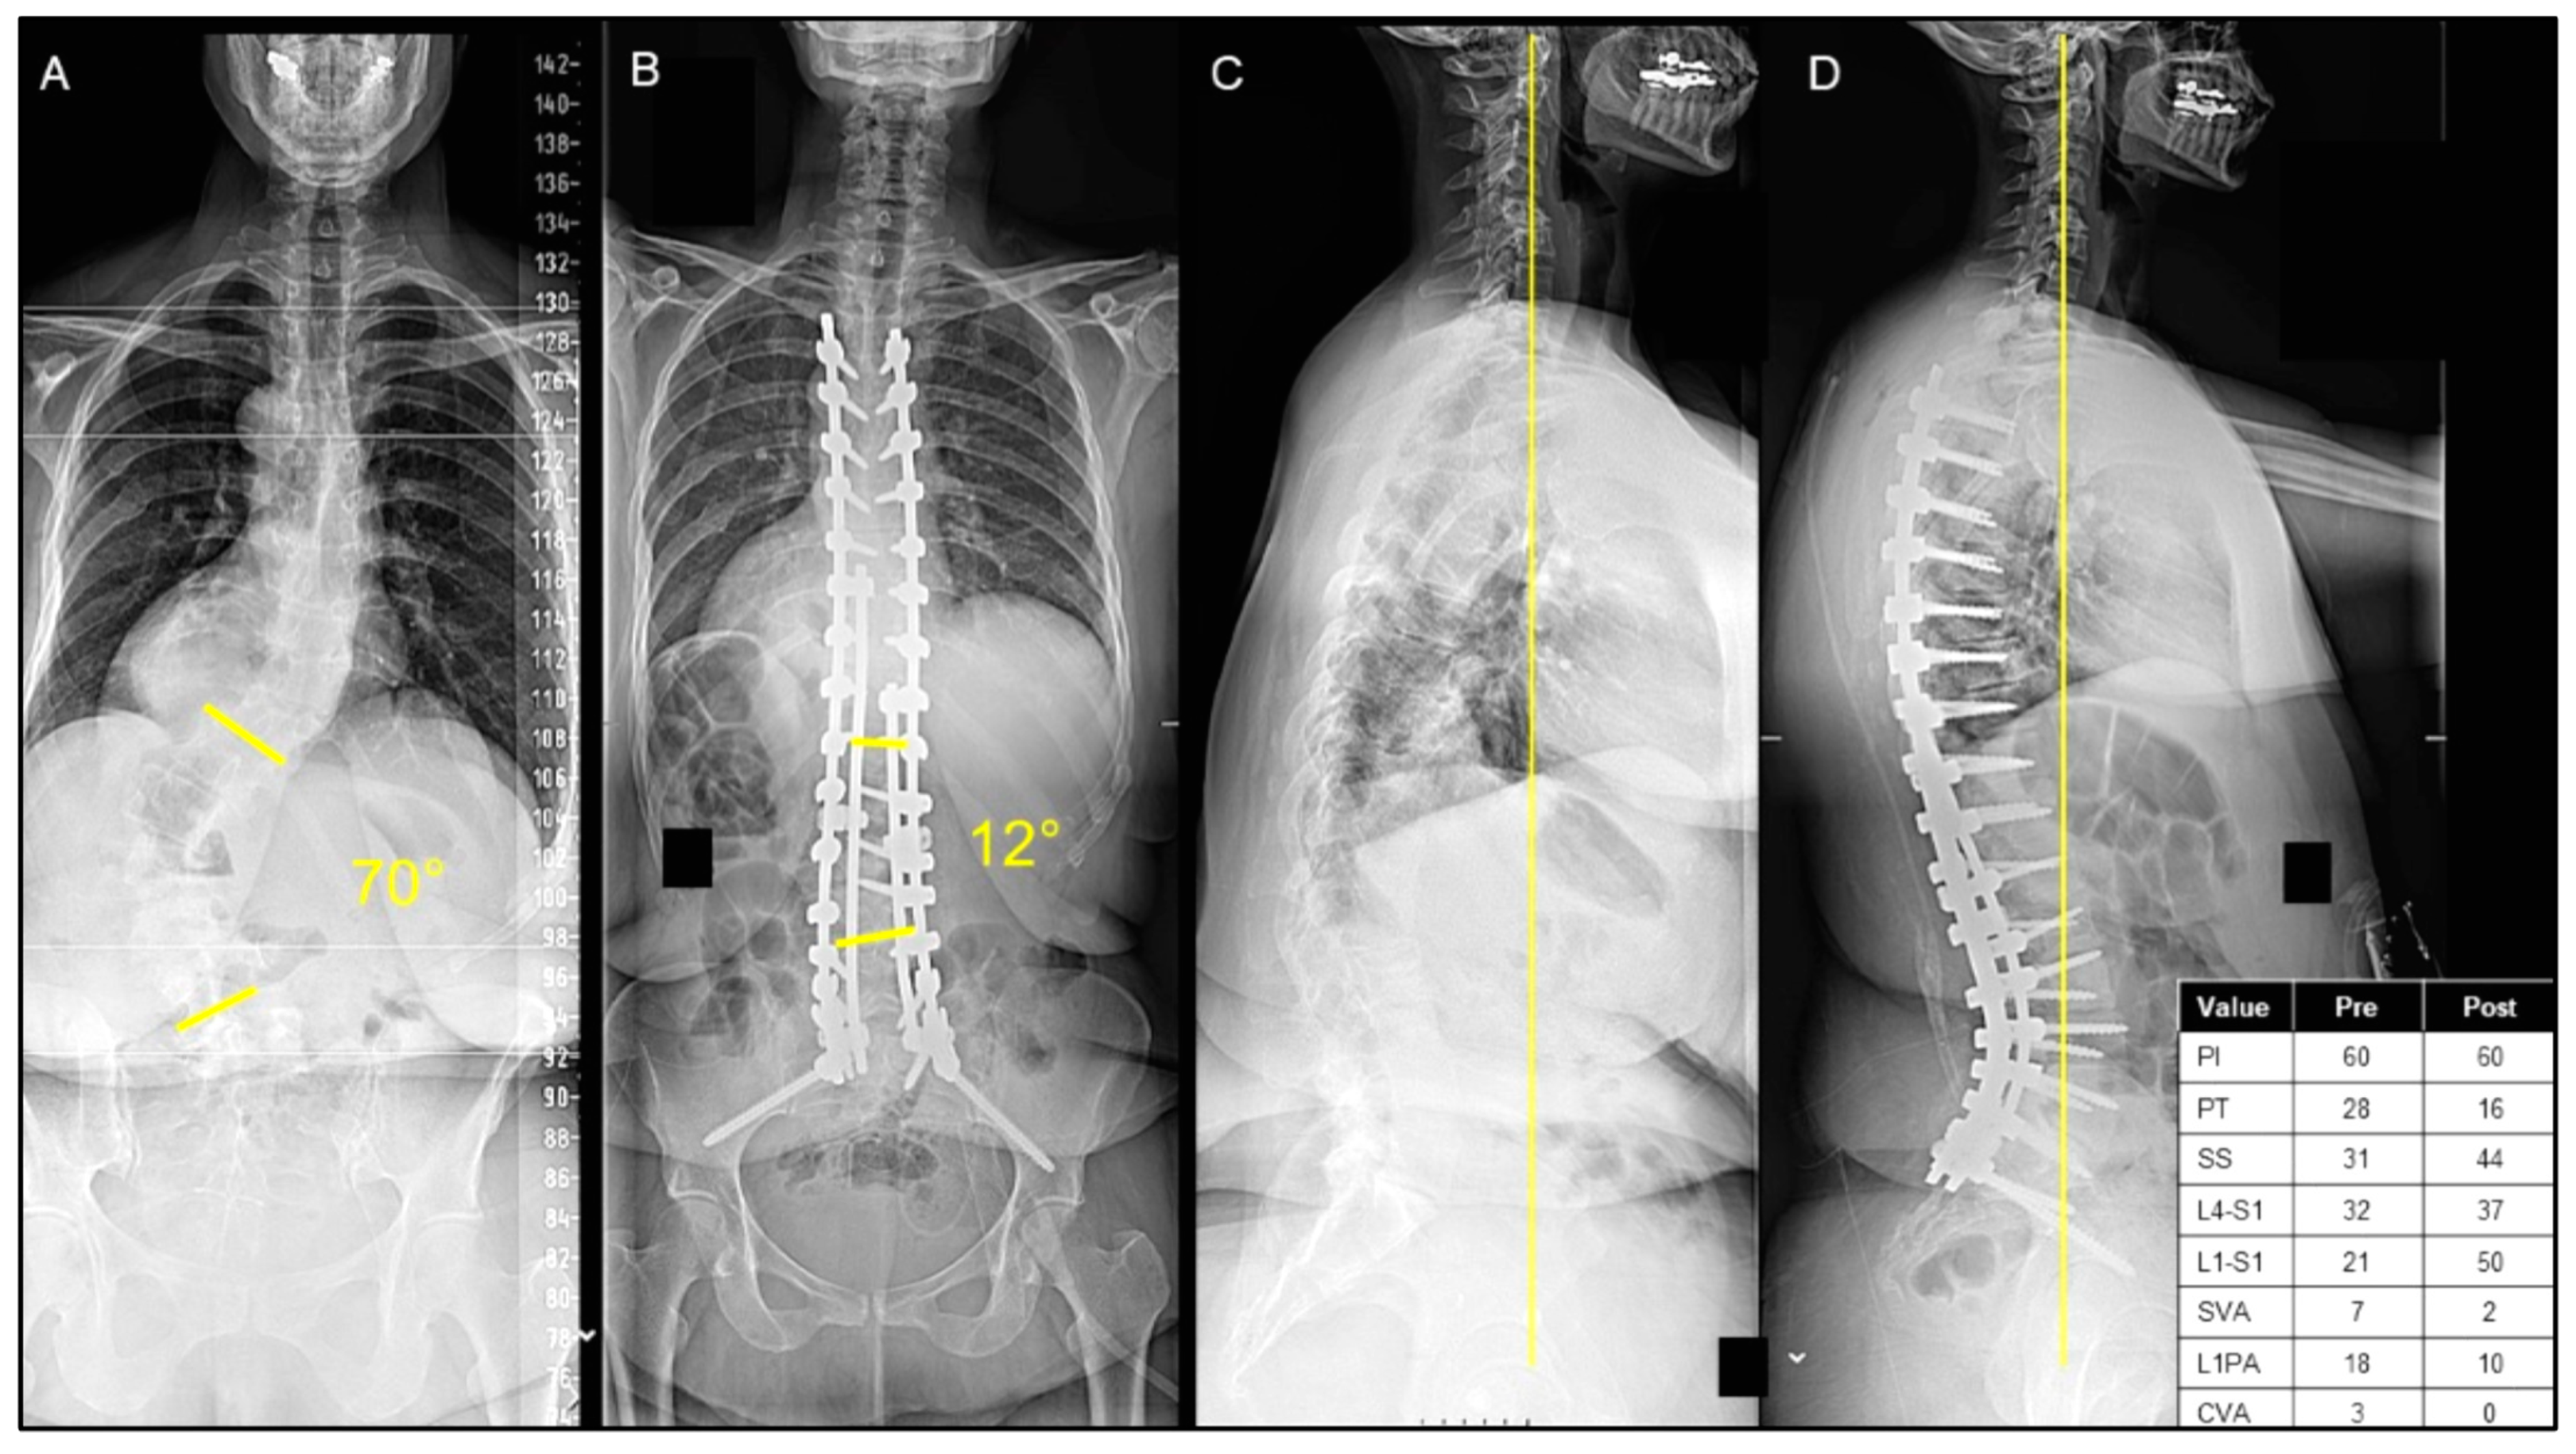

Figure 1.

(A–D) A case presentation of a 49-year-old female presenting with adult idiopathic scoliosis and significant back pain with a significant sagittal/coronal malalignment, as seen on posterior–anterior (PA) (A) and lateral X-rays (C). The patient underwent T4 pelvis posterior spinal instrumentation with T11-L5 posterior column osteotomies, as seen on the postoperative PA (B) and lateral X-rays (D). The patient was discharged home on postoperative day 13.